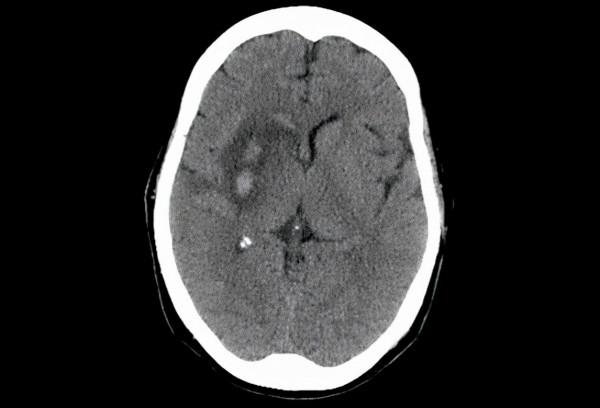

中風

載玻片中的腦部CT掃描(見圖8)顯示右慢樣核中的兩個腦出血區域。中風是美國第五大死因,也是成人殘疾的主要來源。雖然低至中度飲酒與中風風險降低有關,但重度飲酒,無論是慢性還是不規則,都會顯著增加缺血性和出血性中風的風險。除了增加酗酒者頭部外傷的風險外,酒精還具有抗凝血作用。雖然這種效果在較低的飲酒水平下可能是保護性的,但它被認為是在較高消費水平下出血性中風風險增加的部分原因。